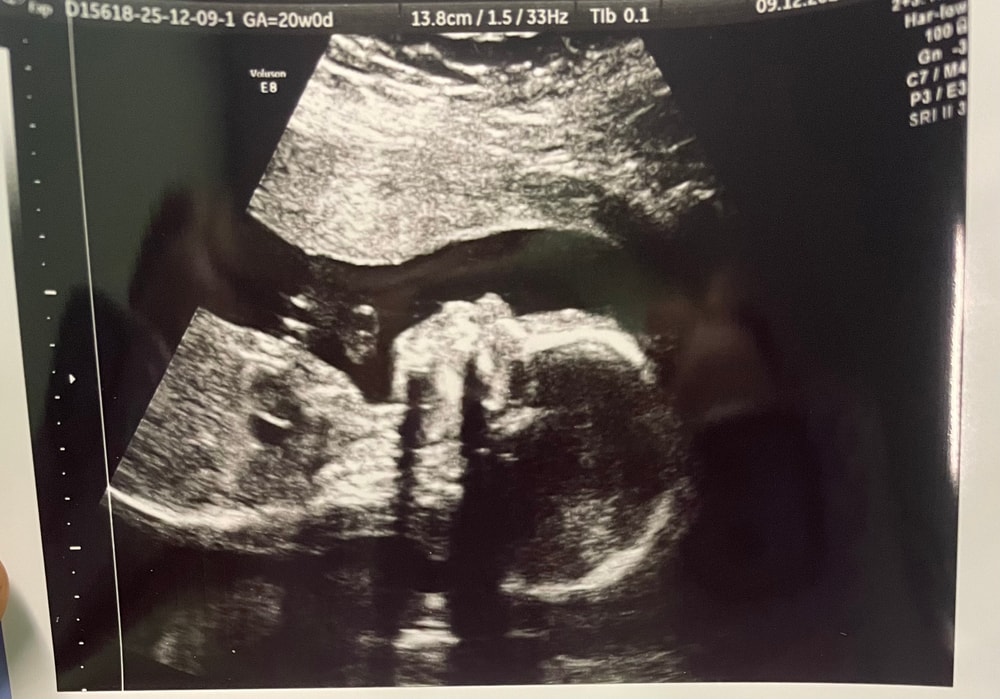

Второй скрининг провели в медцентре г. Якутска, 09.12.2025.

Ну и изображение с УЗИ на память😊

У нас уже четко виден носик папы 😍🥰